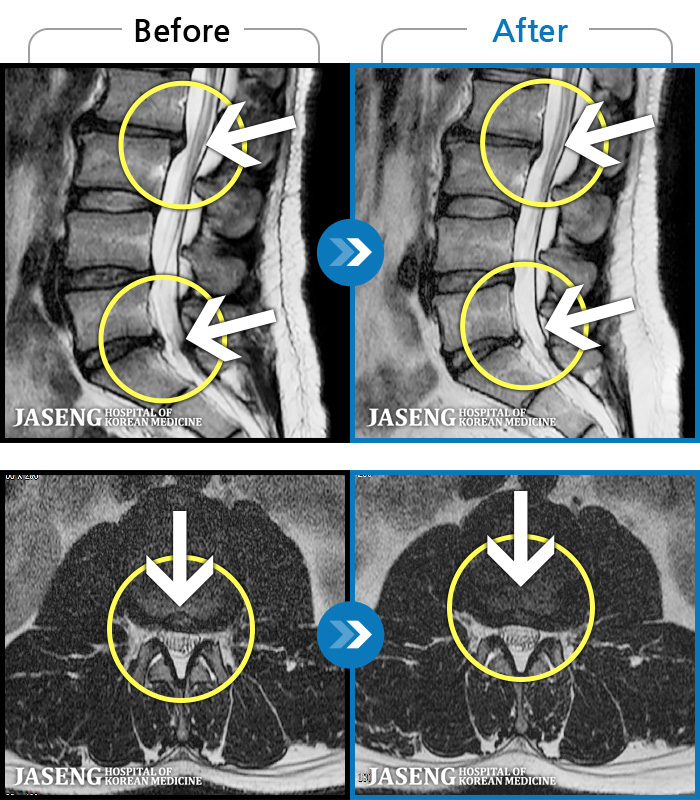

MRI ġ

1,237 MRI ũ ʸ Ȯϼ.